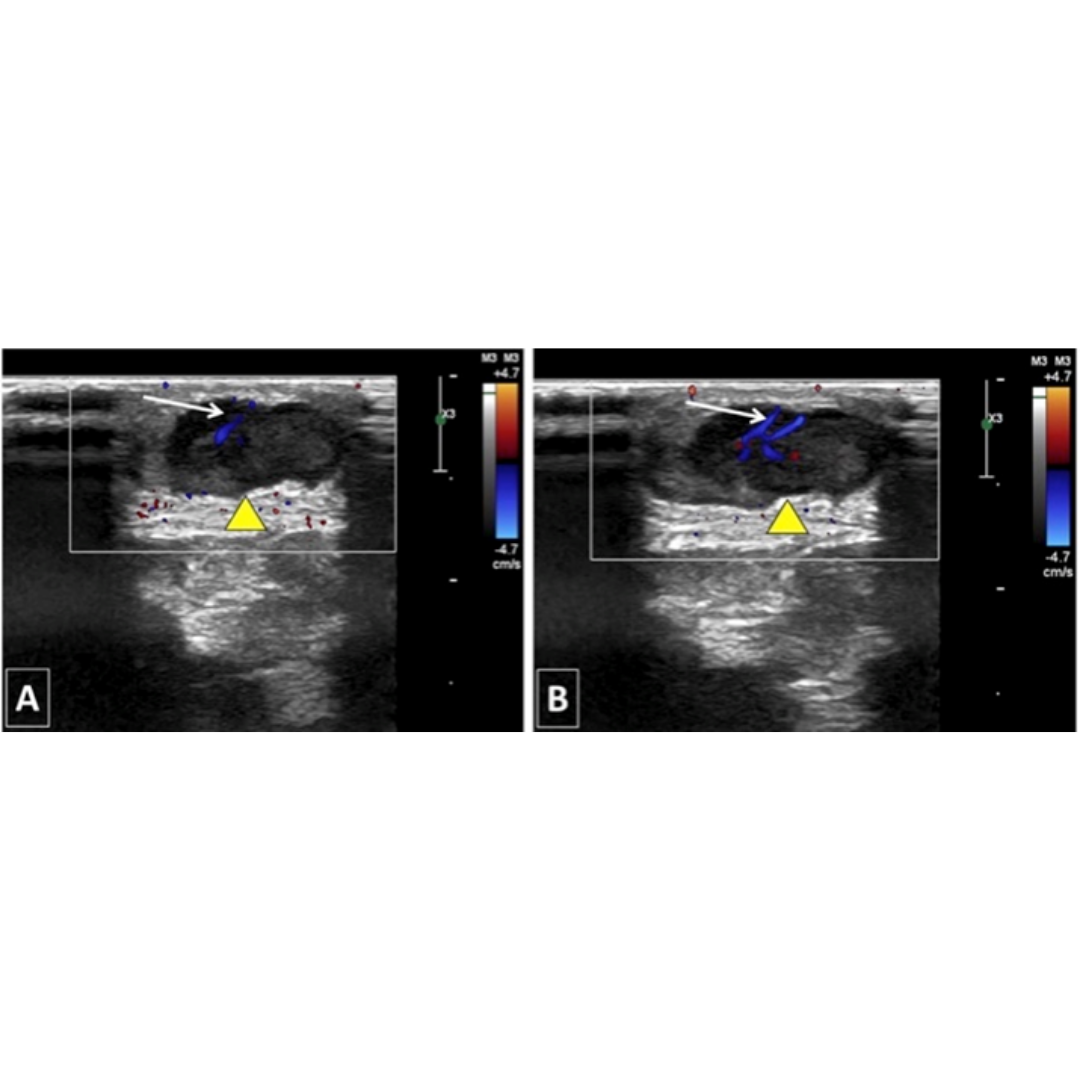

Nódulo hipoecogénico, de apariencia similar a un tracto lobulado, bien definido en hipodermis, al Doppler presenta flujo periférico y central (imagen 6).

Imagen 6: Nódulo hipoecogénico ubicado en hipodermis, de presentación lobulada, con flujo al Doppler color interno.